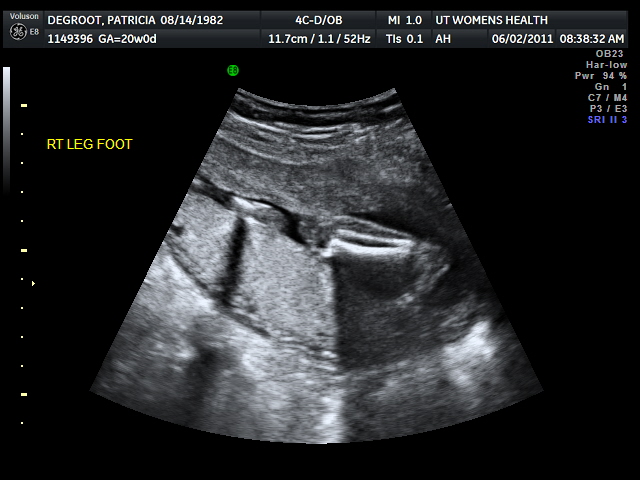

| This was particularly fun to watch...baby was playing with his/her toes! |